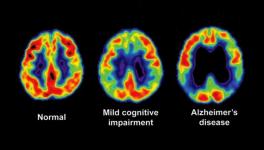

Brain Cells’ Ability to Revamp Genetic Architecture Could be Link to Alzheimer’s: New Study

The diversity of human brain function may not be encoded within a constant genetic blueprint; neurons can reshuffle their genes, a new study published in Nature reveals. This modification of the neurons’ genetic architecture may increase the protein variety in the brain, but it may also be related to Alzheimer’s disease, the study suggests.

The researchers analysed neurons from six healthy elderly people and seven patients reported to have Alzheimer’s disease. The patients had the most common form of Alzheimer’s - the non-inherited one. The researchers tested whether the brain cells got different forms of the gene for amyloid precursor protein (APP). Amyloid is the protein that forms plaques in the brain cells of people suffering from Alzheimer’s disease. The researchers considered APP as a good candidate because in a previous study they found that the gene for APP can have extra copies in the cells of Alzheimer’s patients. The increase arises from the process of somatic gene recombination.

What is more interesting, the Nature paper reports that the APP gene doesn’t make one or two extra copies, in fact, it produces thousands of different versions of the gene. In some of the versions, single nucleotide bases, the building blocks of the genetic code, are switched while in other versions they found that a portion of the DNA is removed and the remaining portions knitted together. They confirmed that neurons of Alzheimer’s patients contain six times more varieties of the APP protein than healthy people.

Somatic gene recombination, the process through which the inherited gene sequences are changed in the lifetime, is the way the neurons change their genetic architecture. Somatic recombination has been observed in some types of cells earlier and also in carcinogenesis—cancer formation, but existence of this recombination process in brain cells has been reported for the first time in this study.